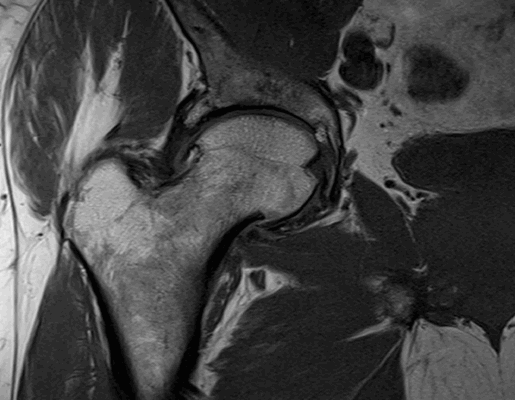

МРТ тазобедренного сустава при феморо-ацетабулярном импинджмет-синдроме показывает возможные причины заболевания:

врожденные пороки развития;

осложнения после травм и оперативных вмешательств;

сопутствующий аваскулярный некроз головки бедра;

воспалительные процессы в синовиальной сумке;

остеохондропатию (болезнь Пертерса);

эпифизеолиз (перелом Салтера-Харриса);

атрофированные мышцы вокруг сочленения и пр.